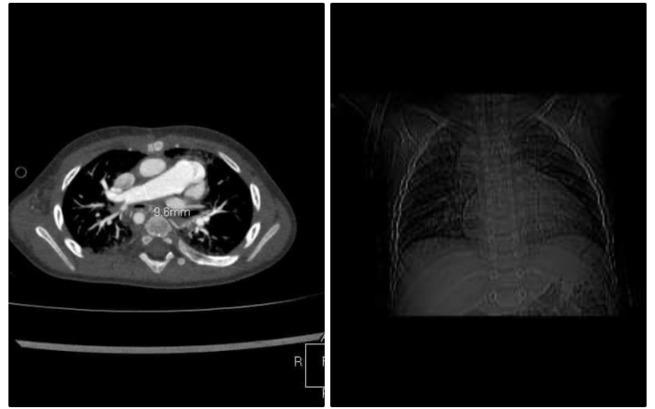

Antosiowi grozi nadciśnienie płucne. Jedno płuco dostaje tylko 10% krwi, natomiast drugie 90%. Prawa tętnica bardzo się powiększyła i na dodatek tworzą się krążenia oboczne. Jeśli na czas nie wyjedziemy i Antoś nie będzie operowany już teraz... Ziści się najgorszy scenariusz!

Przez ostatnie 6 miesięcy żyliśmy nadzieją, że to, co najgorsze, jest już za nami, że z naszym synkiem nie jest aż tak źle, jak mówią lekarze. Niestety, ostatnia wizyta kardiologiczna i badania echo serca oraz angio wykazały, że jednak musimy szukać pomocy za granicą, ponieważ żaden lekarz w Polsce nie jest wstanie zoperować serca naszego synka. Badania wykazały najgorszą diagnozę - lewa tętnica płuca przestała pracować. Antek żyje tylko o jednym płucu!